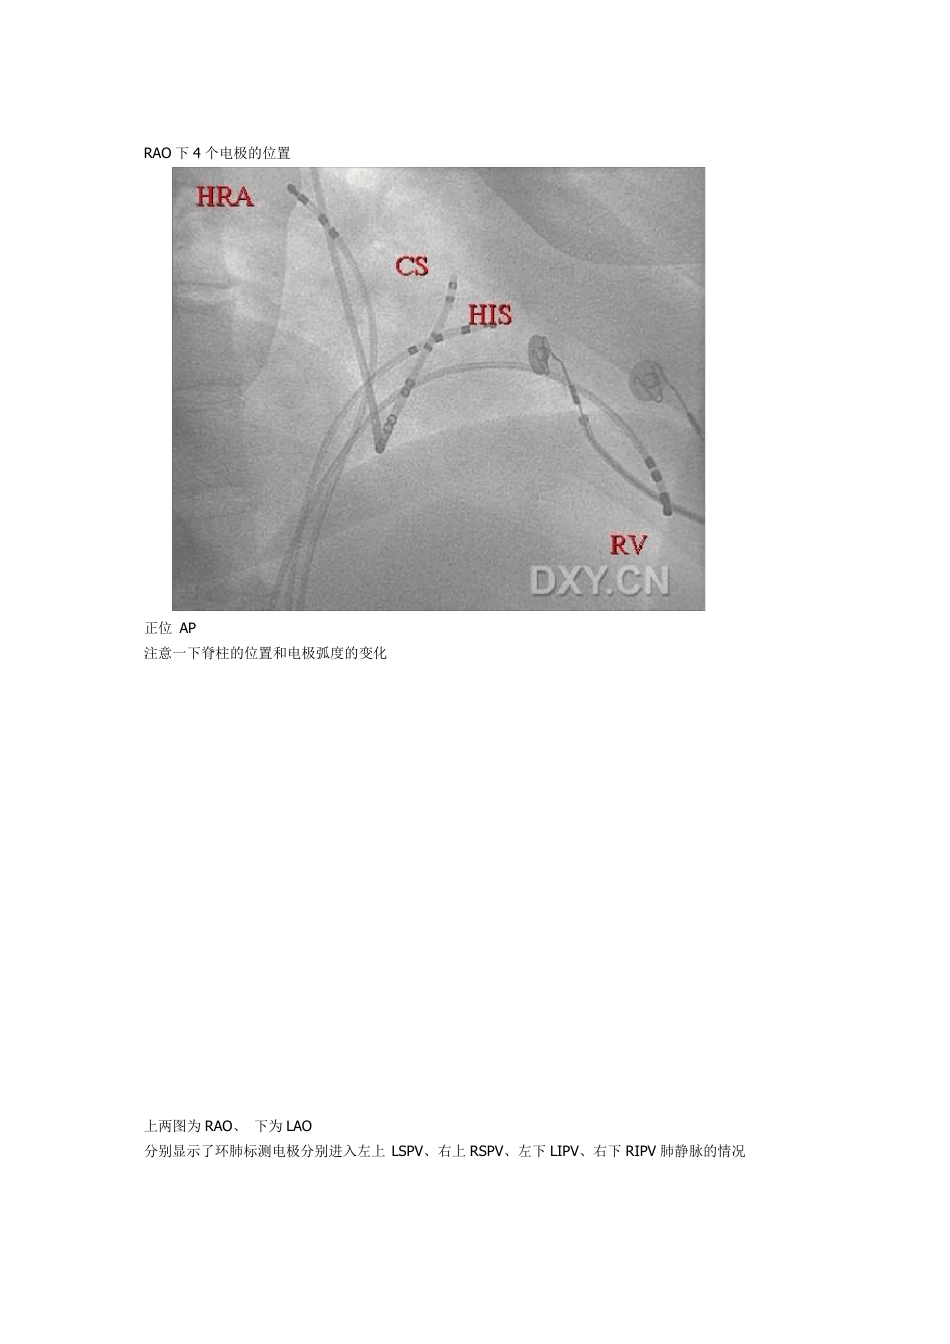

病人需常规穿刺锁骨下静脉,股静脉,必要时穿动脉,常规放置心内电生理电极导管,最长的为高位右房(HR),HIS 束,冠状窦CS,和右室心尖(RV)和射频导管熟称“大头”常规投照体位位左前斜位(LAO) 右前斜位(RAO) 前后位(AP) 和后前位(PA) LAO 下两个瓣环的大概位置 注意 CS 电极的形状 RAO 下4 个电极的位置 正位 AP 注意一下脊柱的位置和电极弧度的变化 上两图为RAO、 下为LAO 分别显示了环肺标测电极分别进入左上LSPV、右上RSPV、左下LIPV、右下RIPV 肺静脉的情况 心律失常的射频消融 已经从原来的二维观察过度到现在的三维重建,目前三维的的操作界面有两种,一种为圣犹达的 Ensite 3000 系统 分NavX 和Array ,NavX 系统为接触式标测,Array 为非接触式标测,就是熟称的“球囊”再有一种就是强生的“CARTO" 介绍一下 Ensite 3000 指导下的常见消融 这是该系统的电极贴片 Ensite 系统采用的是贴片定位技术,分六块贴片,前后、左右、头颈后部,和左大腿内侧 中间的是一个计时模块,一旦激活计时模块,系统便倒计时 18 小时。 这是ensite 系统的组成,想有些同道在导管室已经见过了,但还是给大家看一下 以房颤消融 AF 为例简要说明一下,第一步,导管进入心腔后由于 AF 需要穿房间隔,待穿刺后激活系统,系统可以显示导管在心腔内的位置,注意,图中一个长的是放在CS 的冠状窦电极,一个是在心房 4 极电极 这是用导管在建立左心房模型,导管到过的位置就可以被记录下来,这样可以用导管在心腔内勾画一个模型,而且是立体的,图中是建的左房,因为房颤要打左房和肺静脉 也可以让患者先做一个心脏 CT 造影,然后将 CT 导入改系统,先用导管建模,建完后和 CT 的三维成像融 合,下面就是这个过程 这是用导管建的左房和左上和左下肺静脉的过程,图中是在进行左下肺静脉的修模,注意,下面那个是CS电极做参考 同体位下可任意转动体位,看见肺静脉和左房的交界口,做房颤消融肺静脉的定口非常重要,图中是个头位,注意看肺静脉和心房的交界处 这是建完模后的左房 这是网格图 这是导管建模和CT 融合后的左房,图中是因为正在做房颤消融后的房速的激动顺序标测,看起来眼花,实际看以从颜色看出哪里最早,图中有个大头的影子,注意看,做完了比这个要好看得多 0 这个费用比较高,一台 AF 下来要5-6 万 RMB 五六万算便宜了,我们这用CARTO,得八万多 详细的EPS 检查...